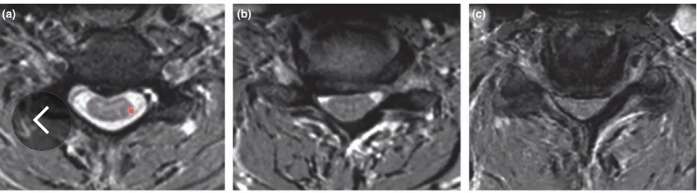

Astrocitoma do canal raquiano

É o mais comum?

Mais em crianças ou adultos?

qual região acomete mais?

Associado a qual sindrome?

Qual diferença mais comum da imagem em comparação ao ependimoma?

A

segundo mais comum

Crianças (90%)

Região cervical

Neurofibromatose tipo I

Imagem: Mais excêntrico e costuma não captar contraste, diferente do ependimoma que capta de maneira muito homogenea